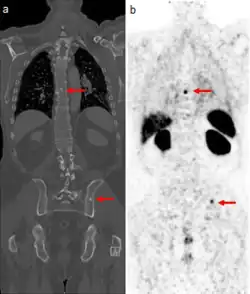

The main (67Ga) technique uses scintigraphy to produce two-dimensional images. After the tracer has been injected, images are typically taken by a gamma camera at 24, 48, and in some cases, 72, and 96 hours later.[21][22] Each set of images takes 30–60 minutes, depending on the size of the area being imaged. The resulting image will have bright areas that collected large amounts of tracer, because inflammation is present or rapid cell division is occurring. Single-photon emission computed tomography (SPECT) images may also be acquired. In some imaging centers, SPECT images may be combined with computed tomography (CT) scan using either fusion software or SPECT/CT hybrid cameras to superimpose both physiological image-information from the gallium scan, and anatomical information from the CT scan.

Gallium DOTA scans

68Ga DOTA conjugated peptides (including 68Ga DOTA-TATE, DOTA-TOC and DOTA-NOC) are used in positron emission tomography (PET) imaging of neuroendocrine tumours (NETs). The scan is similar to the SPECT octreotide scan in that an octreotide-based somatostatin analogue (such as edotreotide) is used as the radioligand, and there are similar indications and uses as octreotide scans, however image quality is significantly improved.[33] Somatostatin receptors are overexpressed in many NETs, so that the 68Ga DOTA conjugated peptide is preferentially taken up in these locations, and visualised on the scan.[34] As well as diagnosis and staging of NETs, 68Ga DOTA conjugated peptide imaging may be used for planning and dosimetry in preparation for lutetium-177 or yttrium-90 DOTA therapy.[35][36]